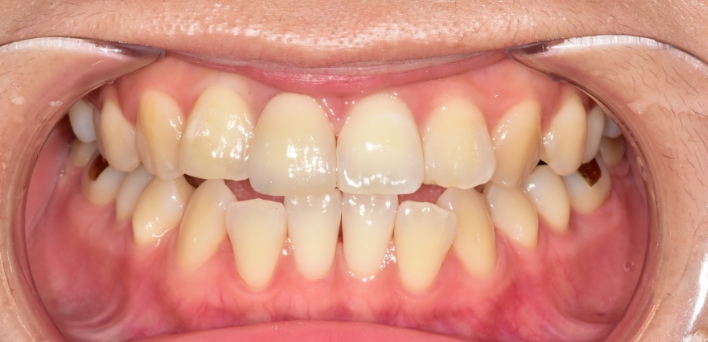

※ 더서울치과의원은 의료법을 준수하며 위 케이스는 실제 환자의 동의를 얻은 사례로 치료 전, 후가 동일한 환경에서 촬영되었습니다.

환자 케이스에 따라 부작용이 발생할 수 있습니다. 이 부분은 의료진의 충분한 상담과 체크를 통해 예방하고 줄일 수 있습니다.

[심미치료 부작용] 시술 후 치아 시림, 보철물 파손 등의 부작용이 발생할 수 있어 개인별 치아 상태에 따른 정확한 진단과 사후 관리가 중요합니다.